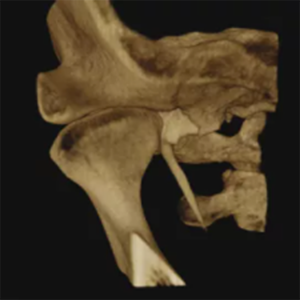

CT / CEPH / PAN Dental CBCT Functions

The LargeV CBCT supports CT, CEPH, and panoramic imaging in one compact system.

It delivers sharp, high-contrast images that reveal every dental structure with exceptional clarity.